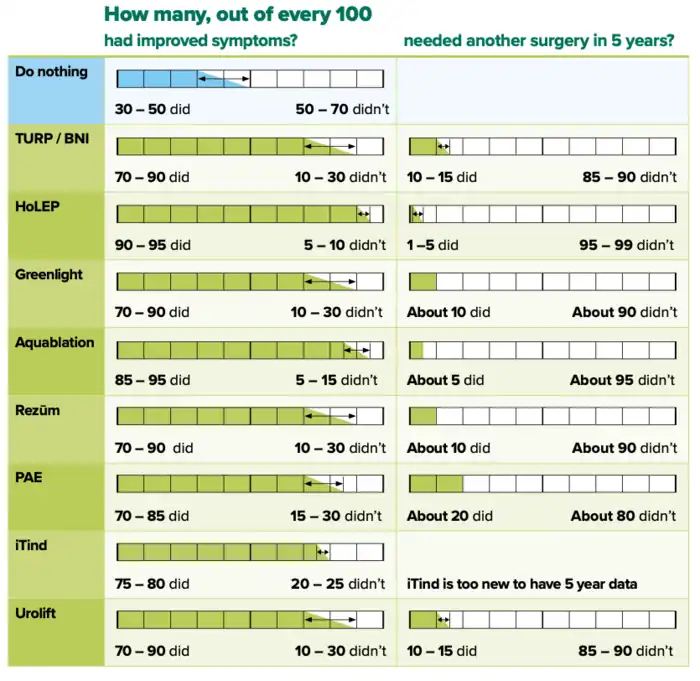

- ^ a b c d e f g "NHS England » Decision support tool: making a decision about enlarged prostate (BPE)". www.england.nhs.uk. Retrieved 8 September 2024.